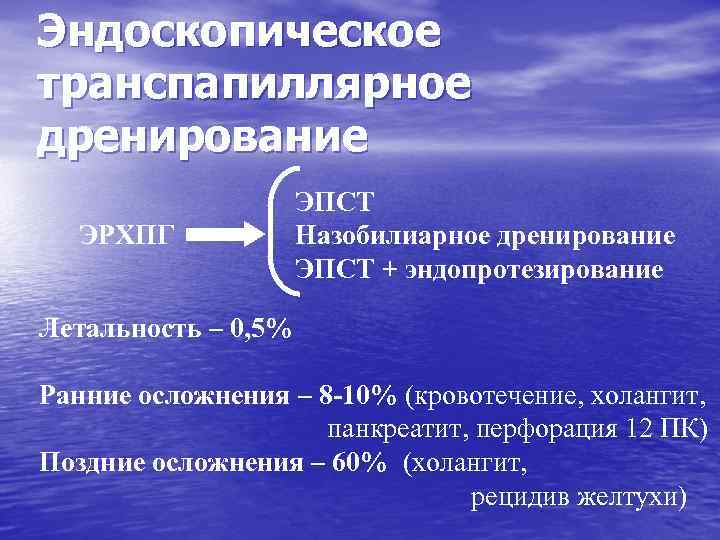

Эндоскопическое транспапиллярное дренирование ЭРХПГ ЭПСТ Назобилиарное дренирование ЭПСТ + эндопротезирование Летальность – 0, 5% Ранние осложнения – 8 -10% (кровотечение, холангит, панкреатит, перфорация 12 ПК) Поздние осложнения – 60% (холангит, рецидив желтухи)